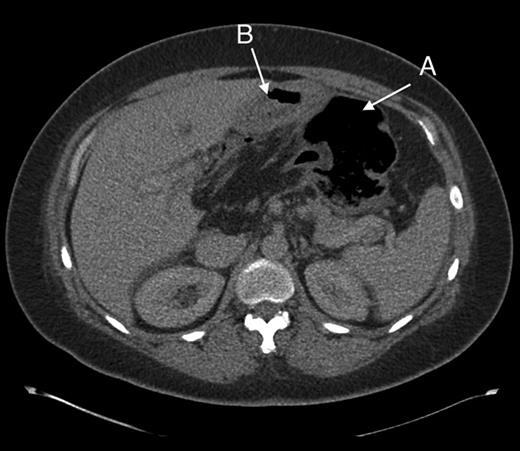

Computed tomography was used for diagnosis. Although initially reported as caecal volvulus, in hindsight there were features indicative of the herniation. (Figs 2 and 3).

Coronal section showing part of the colon passing behind the portal vessels (C) and a distended caecum in the lesser sac (D).